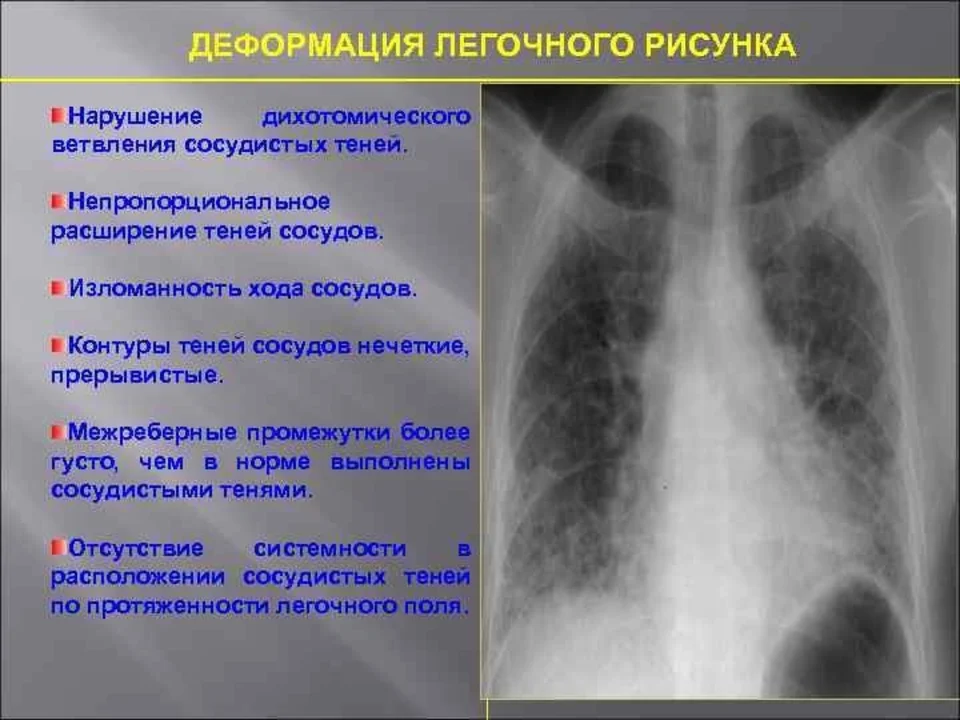

Ячеистая деформация легочного рисунка: медицинская визуализация